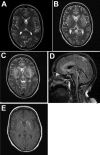

Description:Limbic encephalitis is commonly regarded as an autoimmune-mediated disease. However, after the recent detection of zoonotic variegated squirrel bornavirus 1 in a Prevost's squirrel (Callosciurus prevostii) in a zoo in northern Germany, we retrospectively investigated a fatal case in an autoantibody-seronegative animal caretaker who had worked at that zoo. The virus had been discovered in 2015 as the cause of a cluster of cases of fatal encephalitis among breeders of variegated squirrels (Sciurus variegatoides) in eastern Germany. Molecular assays and immunohistochemistry detected a limbic distribution of the virus in brain tissue of the animal caretaker. Phylogenetic analyses demonstrated a spillover infection from the Prevost's squirrel. Antibodies against bornaviruses were detected in the patient's cerebrospinal fluid by immunofluorescence and newly developed ELISAs and immunoblot. The putative antigenic epitope was identified on the viral nucleoprotein. Other zoo workers were not infected; however, avoidance of direct contact with exotic squirrels and screening of squirrels are recommended.